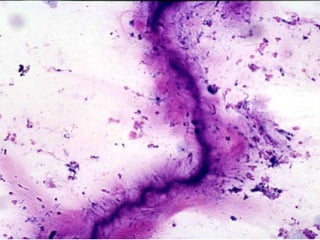

Noneoplastic lung diseaseNoneoplastic lung disease

• Pulmonary alveolar proteinosis

– BAL diagnosis

• Gross: cloudy/milky white with graular

debris

– Paucicellular sample of mononuclear

inflammatory cells

– Amorphous basophilic granular debris

– D/Dx: Pneumocystosis, Nocardia,

amyloidosis

erin pigments in alveolar macropha

Noneoplastic lung diseaseNoneoplasticlung disease • Pulmonary alveolar proteinosis – BAL diagnosis • Gross: cloudy/milky white with graular debris – Paucicellular sample of mononuclear inflammatory cells – Amorphous basophilic granular debris – D/Dx: Pneumocystosis, Nocardia, amyloidosis

• 35.

erin pigments inalveolar macropha